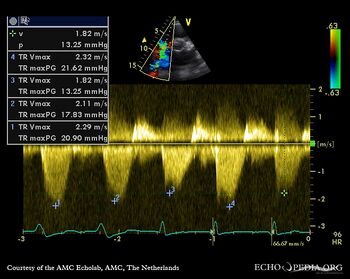

| Continuous-wave signal of tricuspid regurgitation